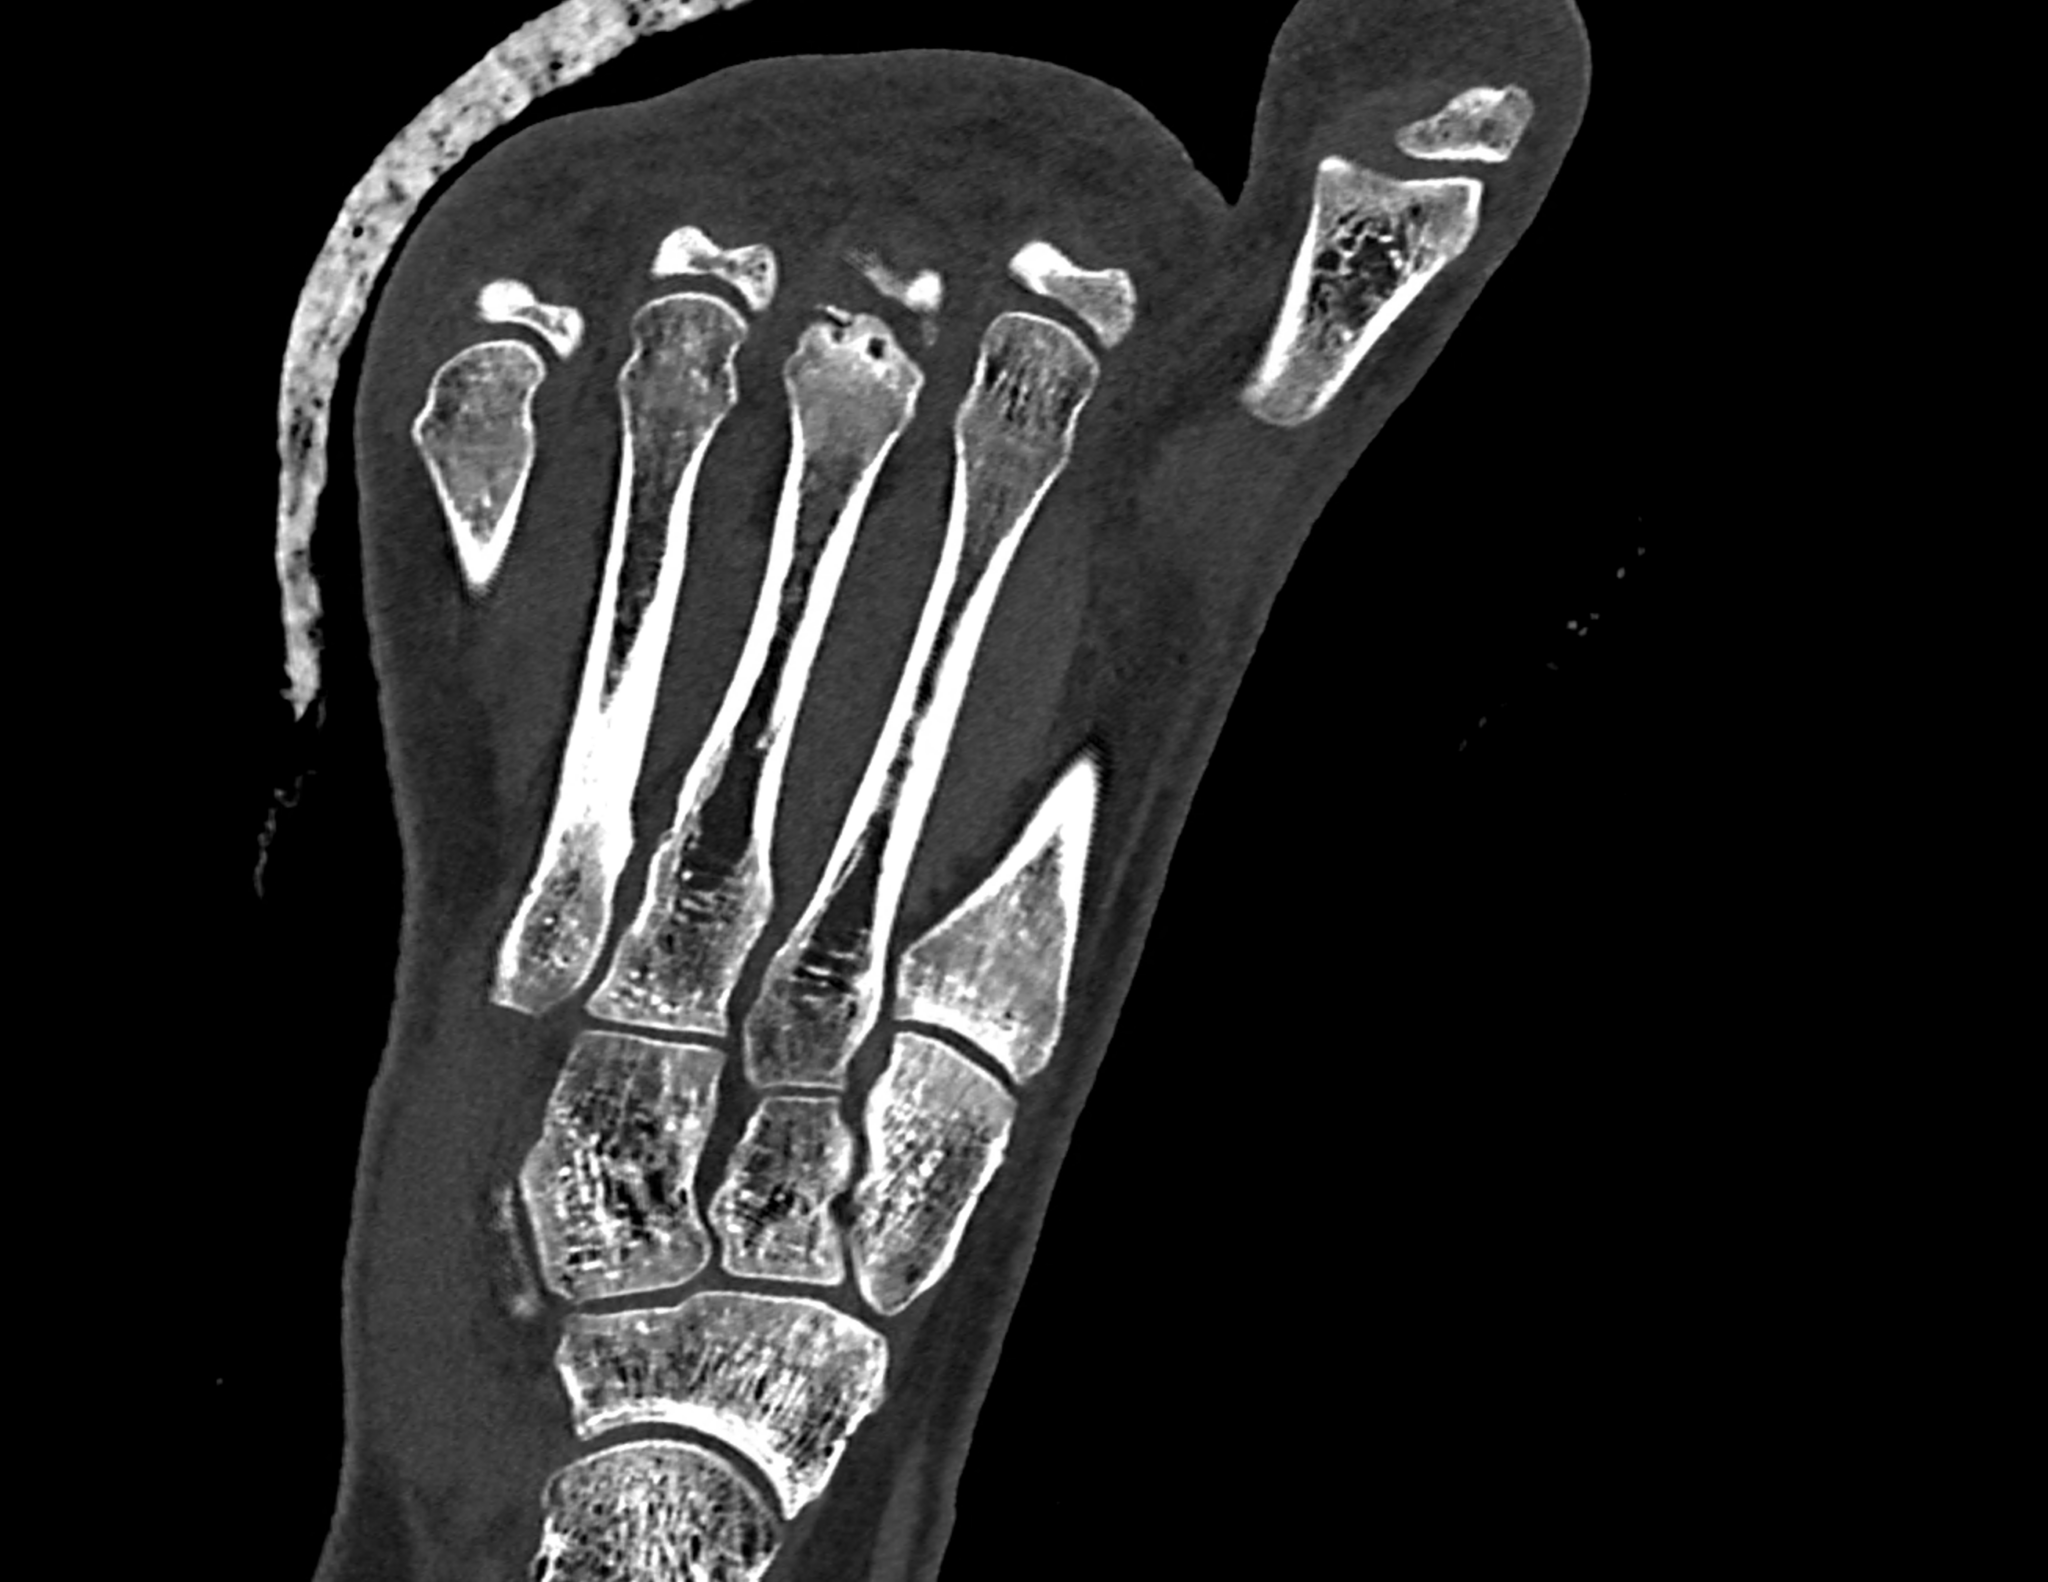

Freiberg-Koehler disease is aseptic necrosis of the head of the second or third metatarsal bone. It is more common in girls during puberty and skeletal maturation, when necrosis of the head occurs, followed by its fragmentation and subsequent deformity of the front part of the foot and the formation of pressure sores. In the acute stage, swelling and pain may occur in the area of the transverse flat arch of the foot. However, it very often progresses without any symptoms and only begins to manifest itself at a later age in connection with transverse flatfoot, with pain and pressure sores under the metatarsal heads in the front part of the foot. In the acute stage in growing children, pain in the front of the foot usually occurs after and following exertion. CT scans show fragmentation and dorsal subluxation of the distal fragments in aseptic necrosis of the metatarsal head more clearly than plain X-rays. Necrosis manifests itself in a changed structure and, in later stages, a significant change in shape; often, significant destruction of the metatarsal head can be seen.

When using ultra-high resolution CT with the smallest possible detector element, even the smallest details of bone changes can be visualized using photon-counting CT. By reconstructing images with a width of 0.2 mm and an overlap of 0.1 mm, there is a significant improvement in resolution in the planes of the reconstructed images in the metatarsal axis in the long axis of the foot, but also in the plane perpendicular to it, which better displays the metatarsophalangeal joint in the laterolateral direction.

two perpendicular multiplayer reconstruction of foot targeted to the third metatarsal head